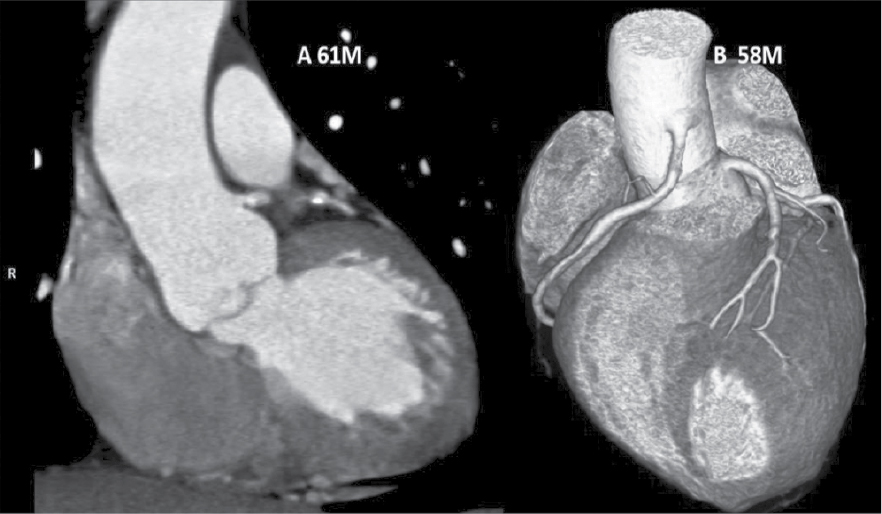

At Nizam’s Institute of Medical Sciences (NIMS), Hyderabad, 770 patients underwent CT-conventional coronary angiography (CAG), on 128-slice single source MDCT (SOMATOM Definition AS ± SEIMENS) during the last 3 years (unpublished data). On analysis, coronary artery anomalies were found in 23 patients (3%). Their ages ranged from 25 to 82 years. Majority of the cases were in 51 to 60 years age group. Among them, 17 were males. The most common anomaly seen was high take-off of coronary arteries, seen in 10 cases. Of them, 2 were having high origin of right coronary artery (RCA) (Fig. 1), 7 were having high origin of left main coronary artery (LMCA) and one was having high origin of both coronary arteries with acute kink at the origin of RCA. Anomalous origin of coronary artery from opposite sinus was seen in 8 cases (Figs. 2-5). RCA from left coronary sinus with interarterial course between aorta and right ventricular outflow tract was seen in 5 cases. Anomalous origin of left coronary artery (LCA) from right coronary sinus with interarterial course between aorta and right ventricular outflow tract was seen in 2 cases. Anomalous origin of left circumflex artery (LCx) from right coronary sinus with retroaortic course was seen in 1 case (Fig. 6). Separate ostia for left anterior descending artery (LAD) and LCx was noted in 3 patients (Figs. 7 and 8). Shepherd crook deformity of proximal segment of RCA was seen in 1 patient. Super-dominant RCA with absent LCx was seen in 1 patient (Fig. 9).

Figure 1. Two different patients of ‘high take-off’ of LCA in patient aged 61/M and RCA in patient aged 58/M.

Most common anomalies are high origin of coronaries from aorta with a normal course. There are cases when RCA arises few millimeters above sinotubular junction, but distance of 2 cm has also been recorded.3 In our experience, there were 10 (1.3%) out of 770 cases with high take-offs. High take-off usually has no clinical problems but may cause difficult cannulation. Incidence is 0.60% as per a study by Fujimoto et al in their series of 5,869 cases.4